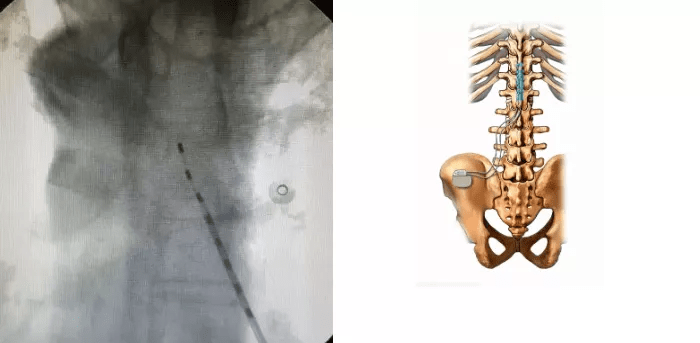

随后 , 在广州医科大学附属第二医院疼痛科 , 高大叔接受了脊髓电刺激术(SCS)治疗 , 经过10余天住院治疗后痊愈 。

文章图片

脊髓电刺激示意图

带状疱疹通常的治疗方式有药物治疗、微创治疗等 。 诸如“脊髓电刺激术(SCS)”“神经脉冲射频术”“局部注射术”等微创治疗术 , 可使疼痛快速得到控制 , 患者恢复快 , 并发症小 , 受到广大患者青睐 。